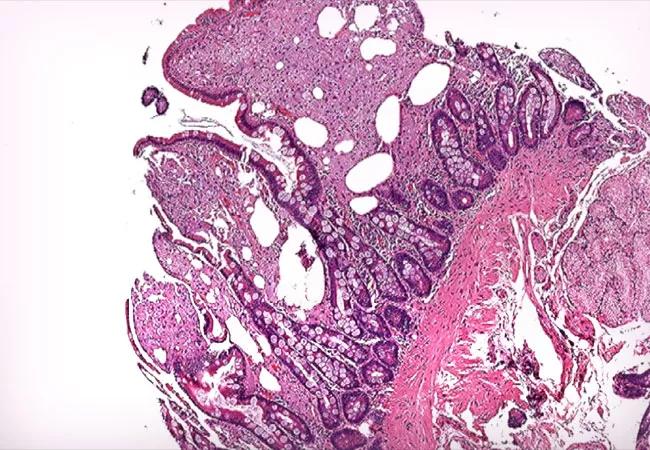

Whipple disease is a rare systemic disease with a very low incidence rate worldwide. Thus, its prevalence is difficult to estimate accurately. It is caused by a gram-positive bacterium, Tropheryma whippelii. The typical clinical manifestations are diarrhea, abdominal pain, weight loss, and fever. In most patients, these are often preceded by articular symptoms. The pathogenesis of Whipple disease is thought to be related to bacterial replication within macrophages, which leads to a systemic immune response and tissue infiltration by the organism. Histologic evaluation is the most common way to confirm the diagnosis. Whipple disease should be part of the differential diagnosis of arthritis, as antibiotic therapy alone leads to a dramatic clinical response.